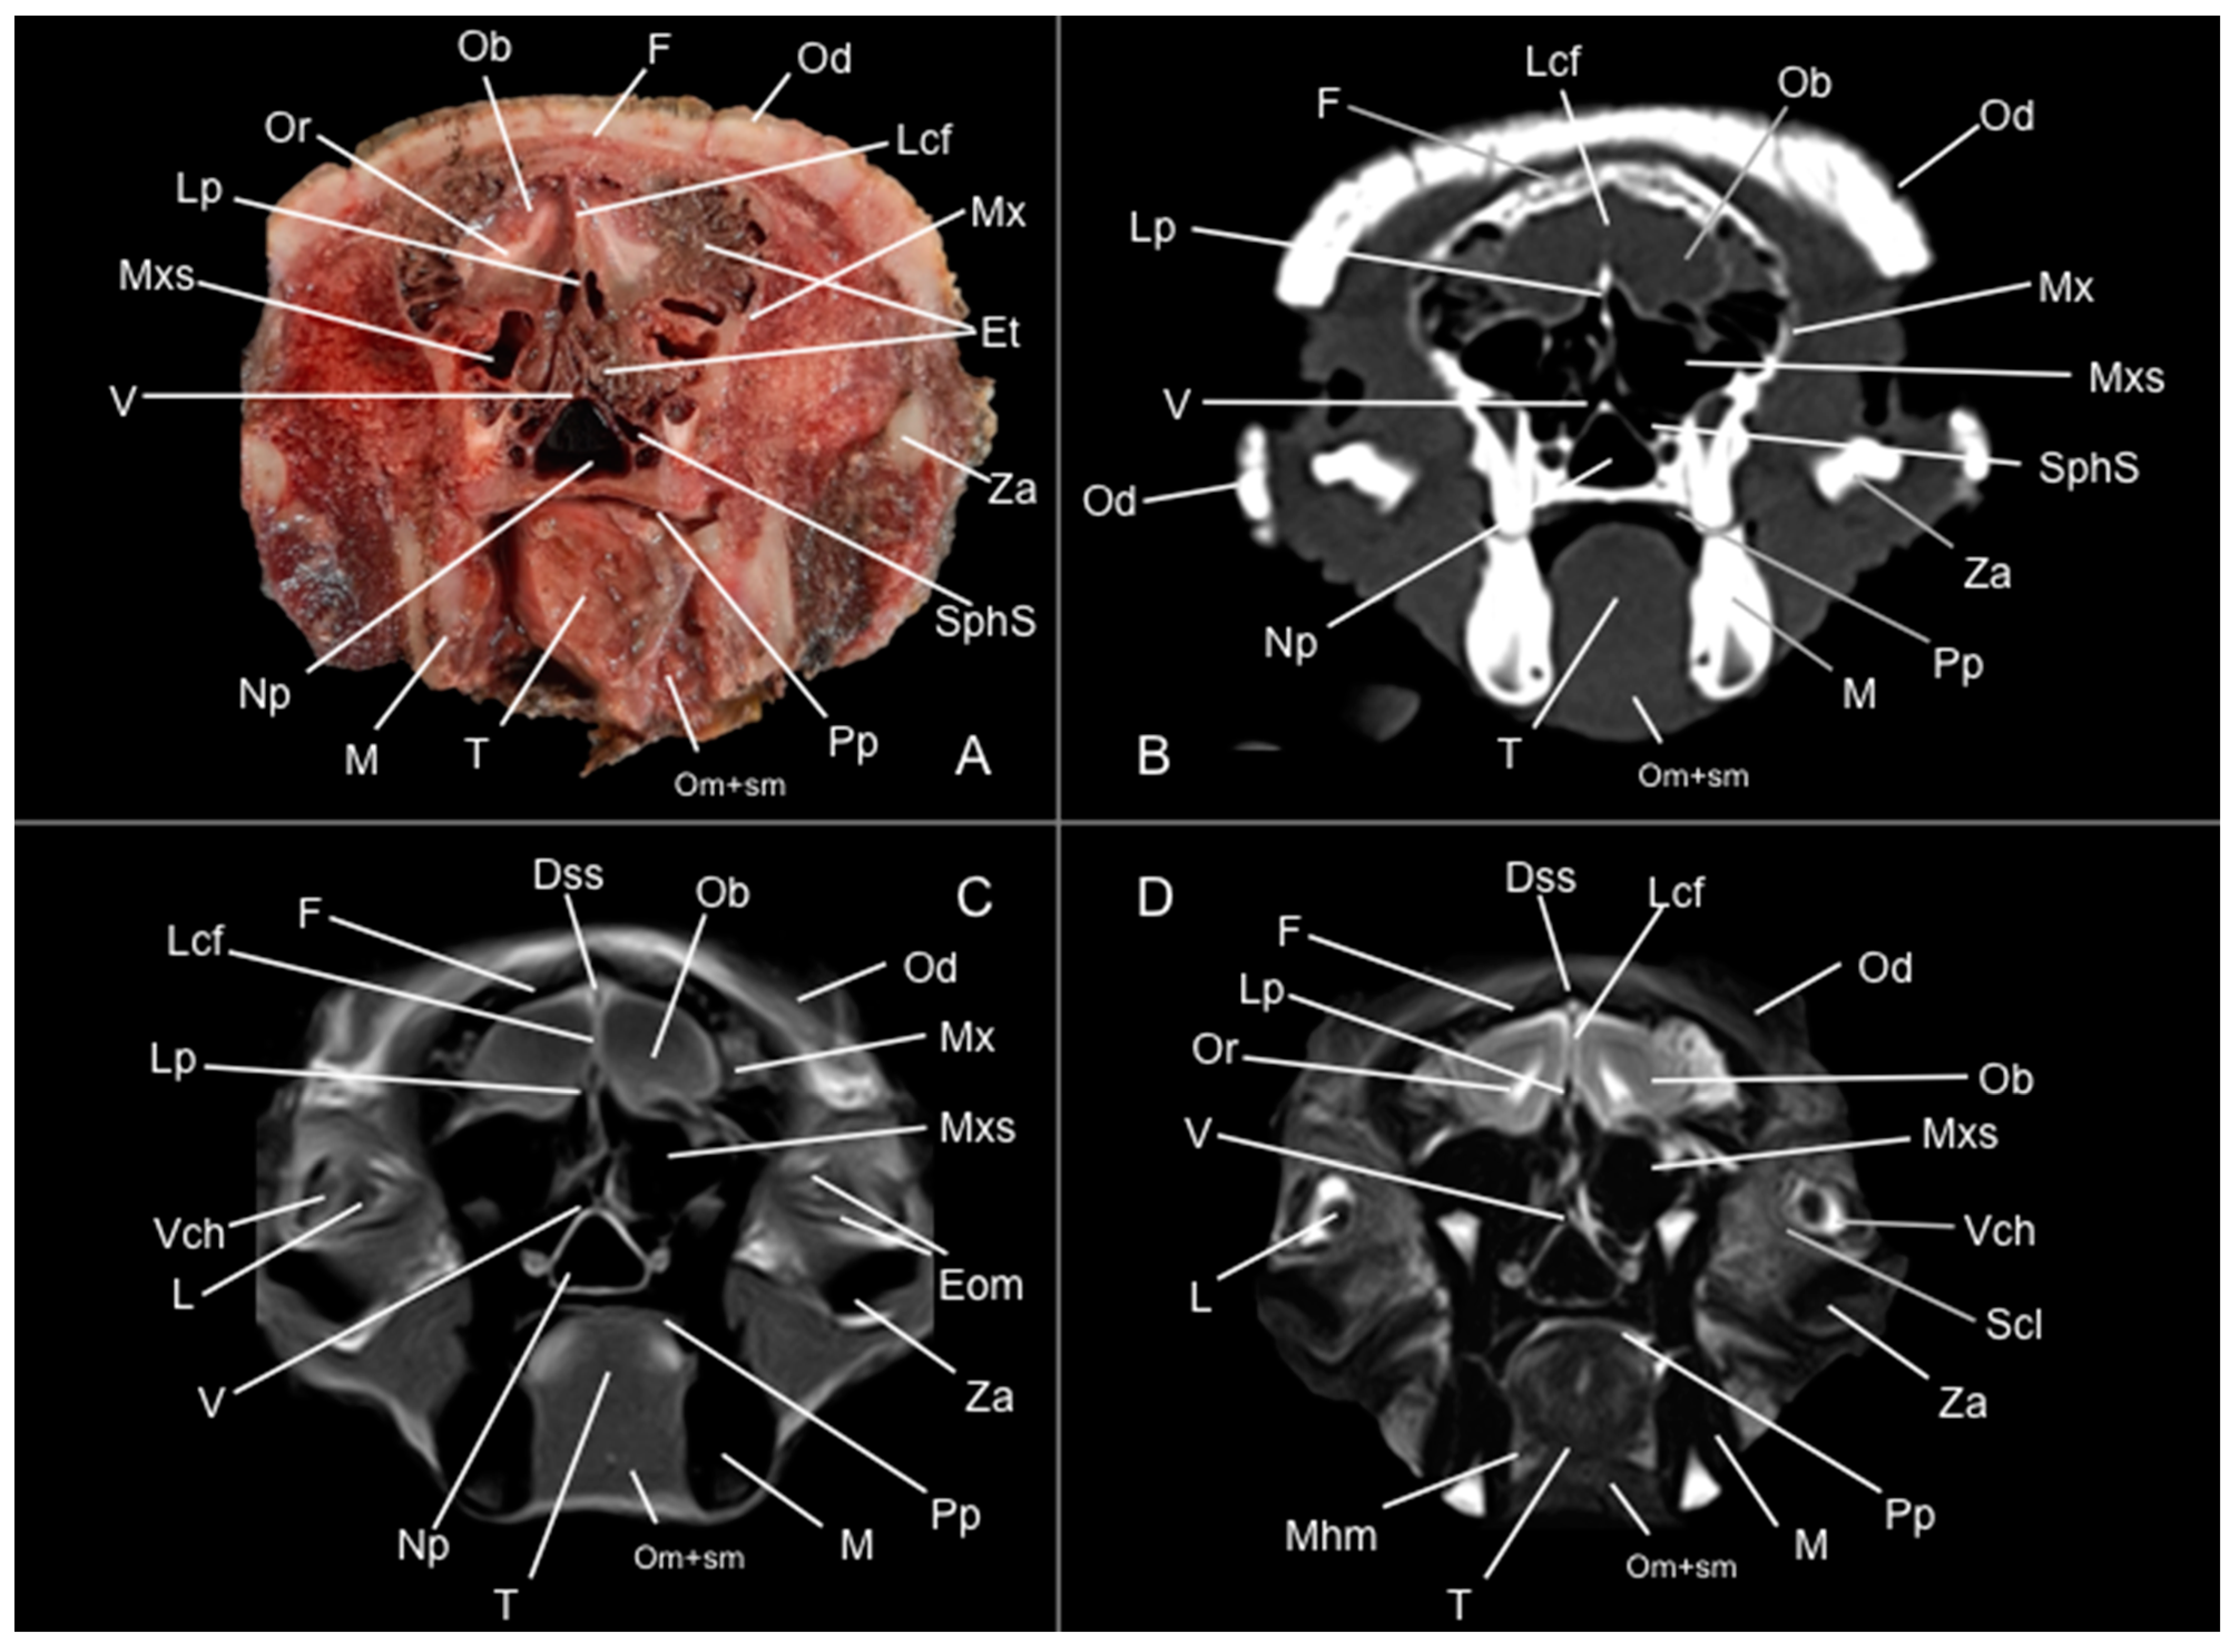

3.1. Anatomical Study

3.2. Computed Tomography Study

3.3. Magnetic Resonance Imaging (MRI)